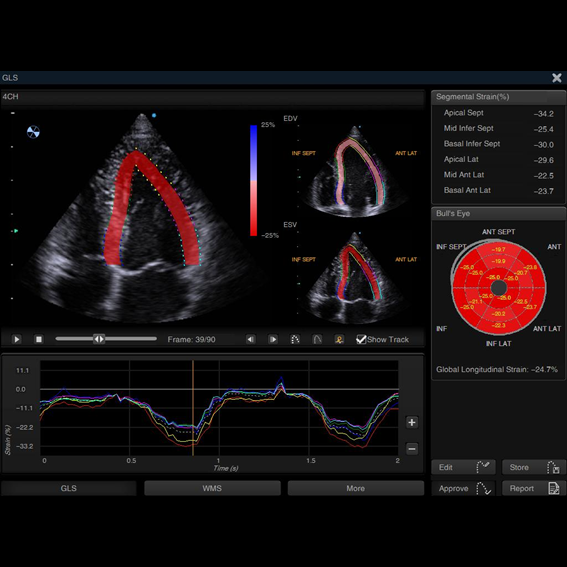

⦁ Strain Rate

⦁ Auto SG

⦁ Auto EF

Tecnologias avançadas

A tela destacável e os softwares de cardiologia compõe com exatidão algumas das tecnologias avançadas que o C7 Plus é capaz de proporcionar ao seu usuário.